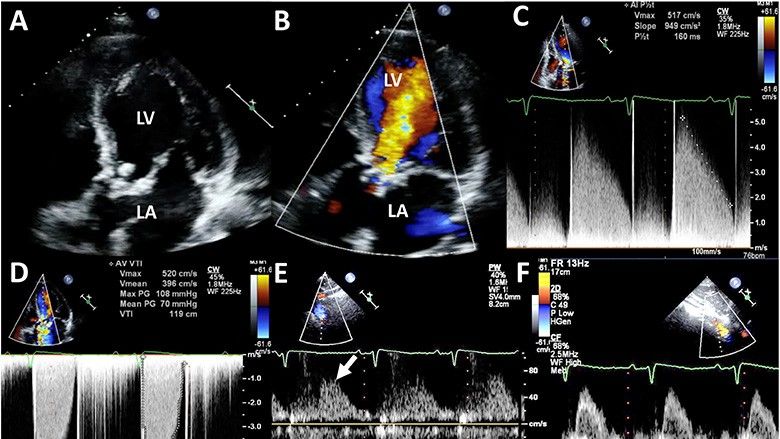

Duke dëgjuar tingujt e zemrës me ndihmën e stetoskopit shfaqet zhurma, e cila mund të ketë një shkallë të ndryshme fuqie dhe përhapjeje. Standardi i artë në diagnostikimin dhe vlerësimin e ashpërsisë së stenozës dhe/ose pamjaftueshmërisë së aortës është ekokardiografia (ekografia e zemrës), e cila mat në kohë reale sipërfaqen e vetë valvulës, shpejtësinë e rrjedhjes së gjakut nëpër vrimën e aortës, si dhe vlerësimi i trashësisë së mureve të barkushes së majtë dhe diametrit të aortës ascendente.